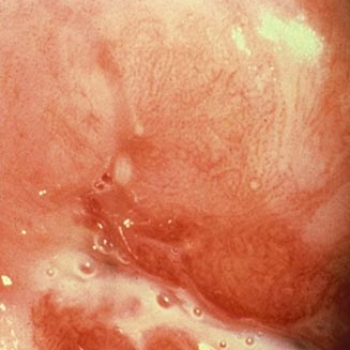

HERPES GENITAL

El Virus del Herpes es muy común en Occidente aunque curiosamente, la mayoría de las personas infectadas no relatan ninguna molestia porque estas son tan leves o pasajeras, que el paciente no las nota.

LAS 12 CLAVES DEL HERPES GENITAL.

Los fuegos vaginales.

El Herpes genital es la enfermedad de trasmisión sexual viral más frecuente en el mundo, sin embargo todavía sigue siendo difícil de diagnosticar.

Virus del herpes I y II

En la década de los ochenta el virus del herpes fue llamado el virus del infiel. Hoy treinta años después conocemos los pormenores de esta infección.